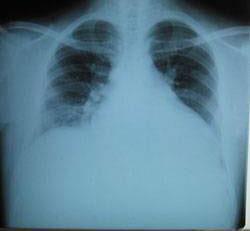

摘要:關于擴張性心肌病的最新治療,小巷深處的隱藏寶藏正逐漸為人們所發(fā)現(xiàn)。通過先進的醫(yī)療技術和方法,擴張性心肌病的治療取得了新的進展。這些治療方法旨在改善心臟功能,提高患者生活質量。小巷深處的醫(yī)療機構或專家可能隱藏著寶貴的治療經驗和方法,為尋求最佳治療方案的病患帶來希望。更多詳細信息需要進一步探索和研究。

擴張性心肌病是一種嚴重的心臟疾病,但“心之港灣”為你帶來希望,這里的專家團隊一直在深入研究擴張性心肌病的最新治療方法,并深知每位患者都渴望得到最佳的治療和關懷,他們努力不懈,為患者帶來生機和新生。